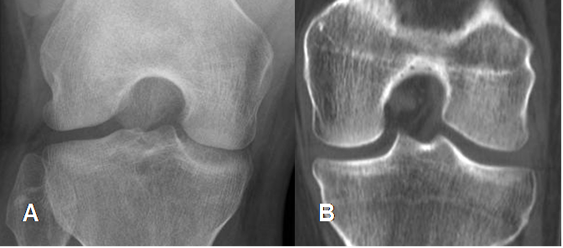

Fig 5. Espacio intercondileo.

A: Rx proyección de túnel o Fick y B: TAC reconstrucción coronal. Espacio intercondileo amplio, sin formación de osteofitos.